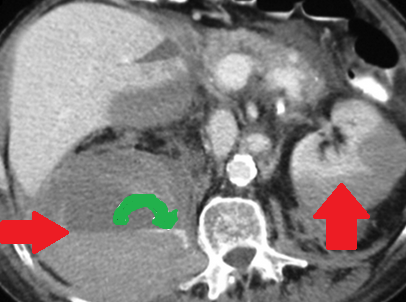

Αριστερό περινεφρικό αιμάτωμα και δεξιό αιμάτωμα λαγονοψοΐτη — αντιπηκτική αγωγή (Ευγενική παραχώρηση Dr. V. Penopoulos)